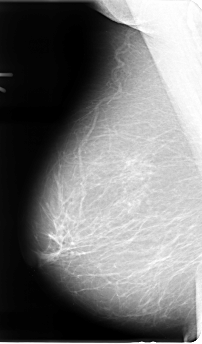

B_3071_1.RIGHT_MLO

ics_version 1.0

filename B-3071-1

DATE_OF_STUDY 11 8 1994

PATIENT_AGE 55

FILM_TYPE REGULAR

DENSITY 2

DATE_DIGITIZED 26 9 1997

DIGITIZER LUMISYS LASER

RIGHT_CC LINES 4808 PIXELS_PER_LINE 2888 BITS_PER_PIXEL 12 RESOLUTION 50 NON_OVERLAY

RIGHT_MLO LINES 4816 PIXELS_PER_LINE 2824 BITS_PER_PIXEL 12 RESOLUTION 50 NON_OVERLAY